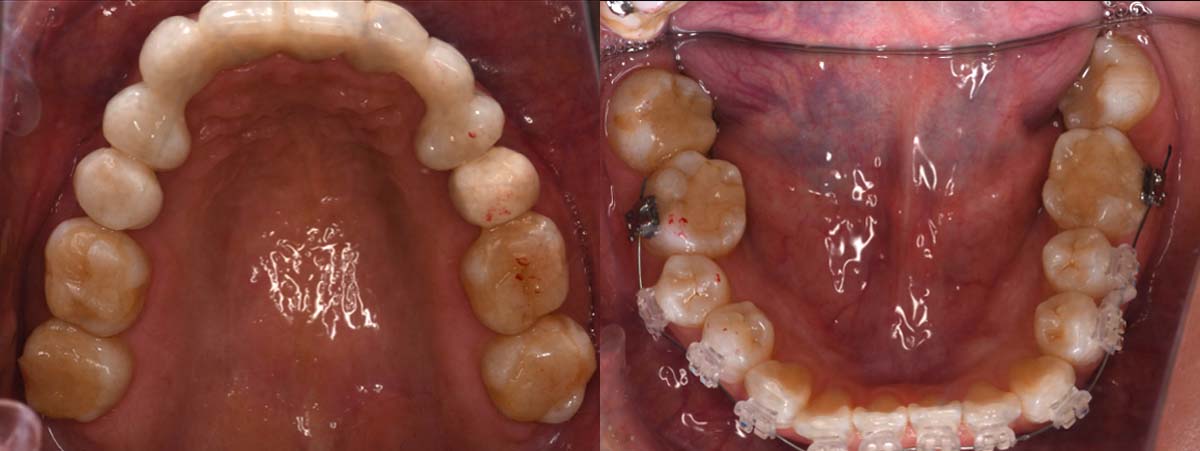

バイトアップ後

2024年 10月 下顎MTM開始